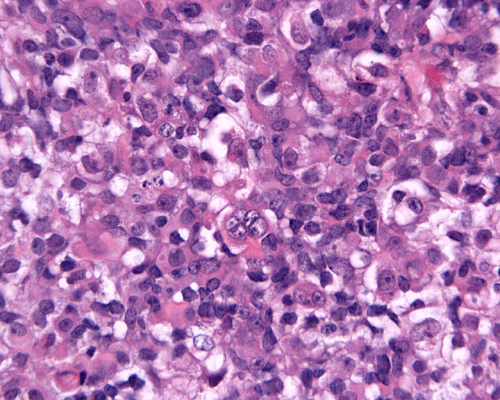

The patient was admitted to our hospital because of a large cerebellar mass that was diagnosed in an outside institution. A surgery was performed. The followings are the representative photos of this mass.

Panel A was a cytologic preparation (squash preparation) and Panel B was the frozen section obtained on intraoperative consultation respectively. Panel C, D, and E were permanent sections obtained from representative areas. Panel F, G and H were cerebellar tissue that was included in the specimen.